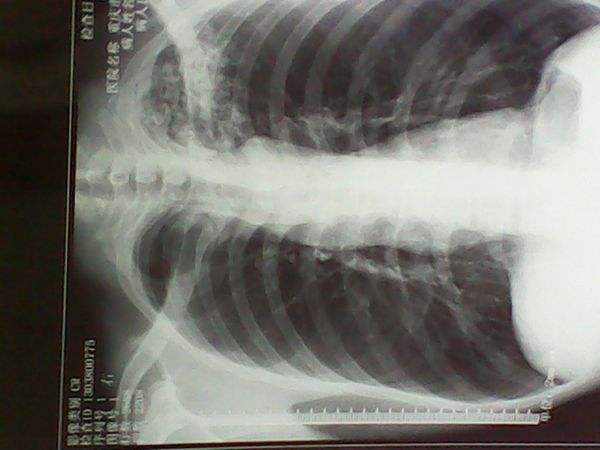

結核菌素試驗、X線檢查

肺結核圖片